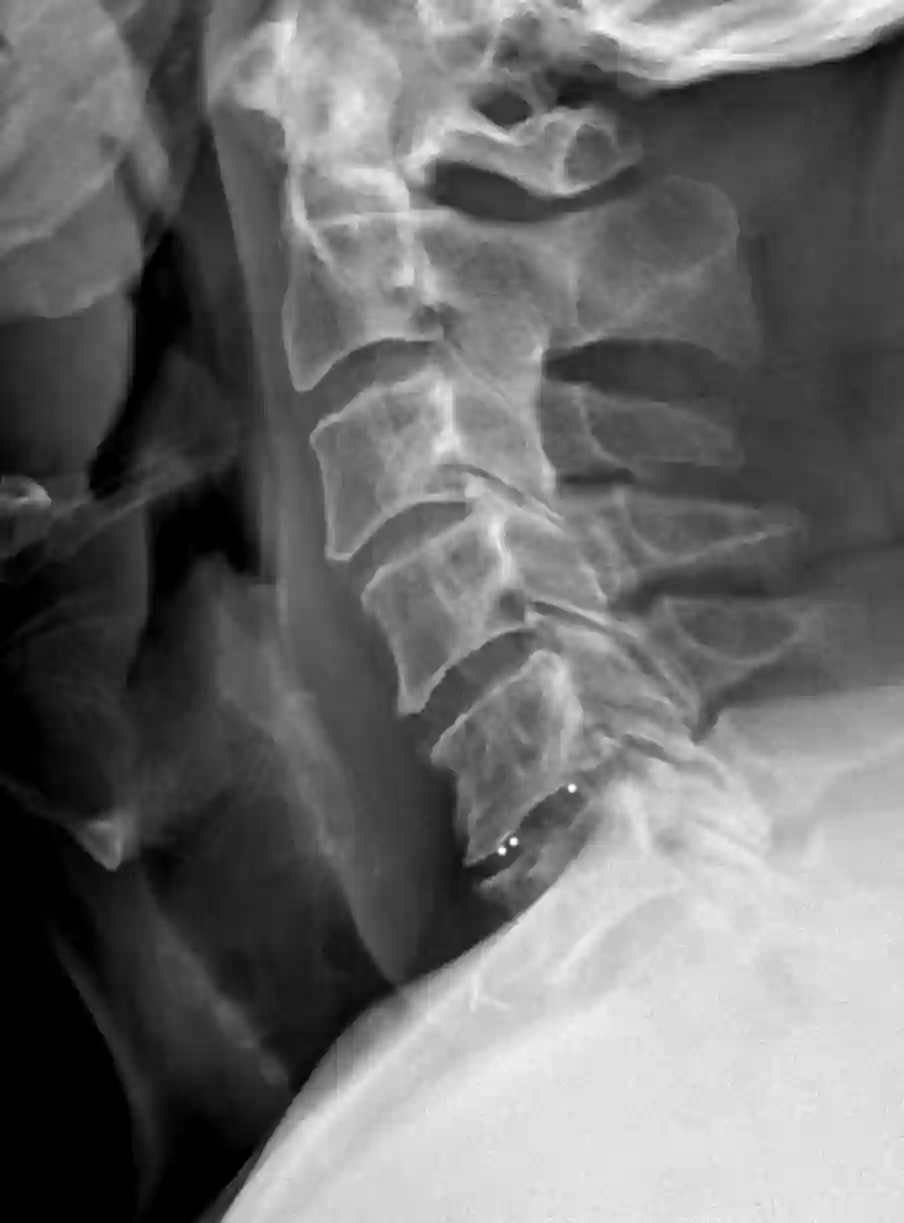

Bildgebung